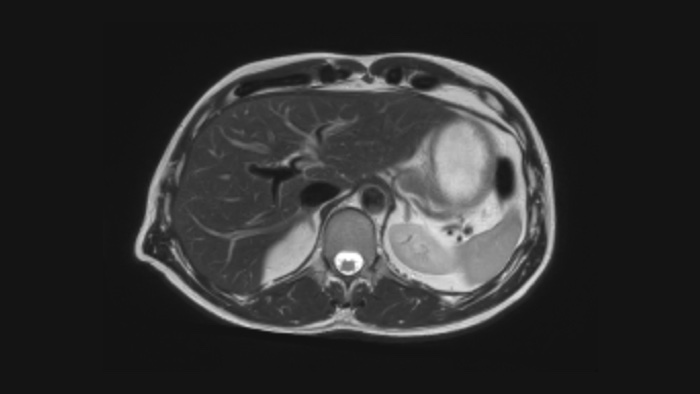

Ahora puede tenerlo todo con Ingenia Ambition. Ofrece la oportunidad de mejorar sus imágenes de resonancia magnética en todos los niveles.

Confianza diagnóstica Ofrece una resolución espacial hasta un 60% más alta en el mismo tiempo de escaneo. 4

Confianza diagnóstica Amplíe su capacidad de obtener imágenes excelentes en todas las áreas clínicas. Vea cómo se benefician sus compañeros.